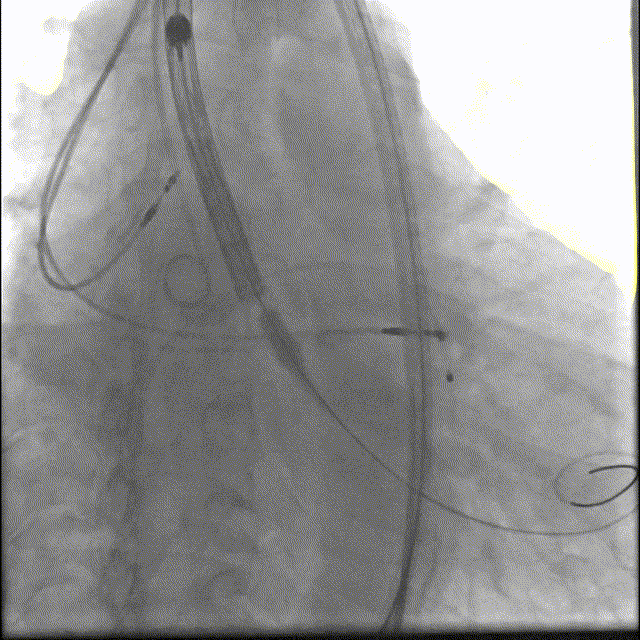

3. 在J型导丝指引下,使用6F pigtail造影导管进入左心室,测得主动脉瓣跨瓣压差15mmHg, 升主动脉血压180/40mmHg, 左心室压力165/5mmHg, 交换为特硬导丝Lunderquist至左心室,结合术前冠脉CT和心脏超声测量的瓣环直径大小,选择VitaFlow Liberty™30可回收瓣膜系统送至主动脉瓣环处,在Pigtail导管定位,主动脉根部造影协助指导下,精准定位,以180次/分快速起搏,逐步释放瓣膜,支架释放后退出导管输送系统,猪尾导管行主动脉根部造影示:人工瓣膜深度4mm, 冠状动脉开口未受影响,食道超声提示无主动脉瓣反流。

VitaFlow Liberty™30瓣膜植入